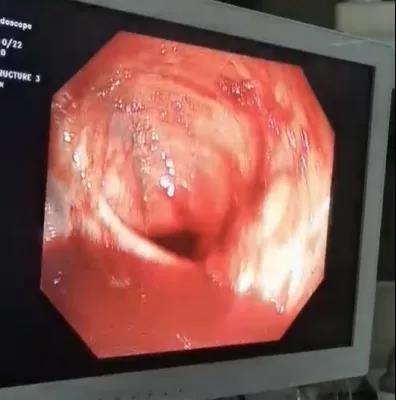

10月14日,患者无明显诱因出现暗红色血便,量约1900ml。通过多学科联合会诊,给予质子泵抑制剂、奥曲肽、反复输血等治疗。但患者仍有暗红色血便,每日50—100ml。7日后患者突然便血1300ml,呈暗红色,伴有血压下降,病情逐渐加重。重症医学科主任医师李冬纯按疑难危重患者的识别标准上报医务科组织全院MDT讨论,考虑下消化道出血,需进一步明确出血原因。经医务科协调,请内镜中心曹鹏副主任会诊,内镜团队4人至重症医学科为患者行床旁肠镜检查。镜下可见肠道内大量出血,反复冲洗肠道,终于在回盲部见“因创伤导致的该部位出血灶”,给予镜下电凝止血治疗。在随后的24小内患者无血便发生,生命体征趋于稳定。